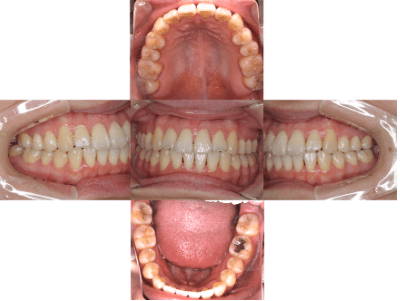

Before

治療前

• 初診時年齢:25歳

• 主訴:開咬

• 診断:舌癖を伴う歯性の開咬、非抜歯

• 治療内容:下で前歯を押してしまい、前歯で咬めない状態でした。マウスピース型カスタムメイド矯正歯科装置(製品名インビザライン 完成物薬機法対象外)で、奥歯を低くしつつ、前歯を伸ばし、前歯で咬めるようになりました。

• 治療期間:2年6ヶ月

• リスク:ブラックトライアングル(歯と歯の間と歯ぐきの間の三角形の隙間)が強くでる場合がある

• 費用:90万円